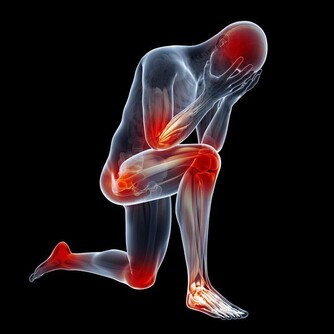

容易產生輕度疾病

具有調節體溫機能的腦下視丘,同時也是控制自律神經及激素的中樞。因此,低體溫會影響自律神經功能以及激素平衡,進而引起肩膀僵硬、頭痛、暈眩、手腳冰冷等症狀。另外,體溫偏低與月經不調、經前症候群等婦科病也有關聯。